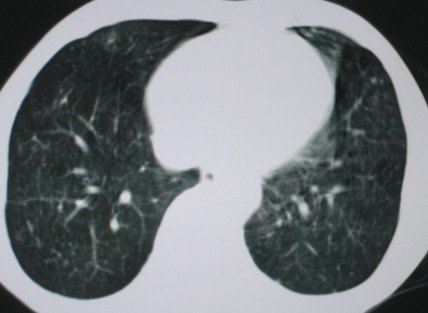

以下是引用医影拾贝在2008-6-3 18:48:00的发言:[br]双上肺弥漫性小结节影,纵隔窗内钙化淋巴结影,考虑血播性tb可能性较大,不除外肺ca可能

以下是引用卜一在2008-6-3 19:33:00的发言:[br]双肺结节,以双上肺分布为多,期间搀杂片状致密影及索条致密影。考虑:继发性肺结核伴血型播散可能性大。不除外肺泡ca的可能!另:椎体退变!

以下是引用panyishengct在2008-6-3 21:09:00的发言:[br]双上肺弥漫性小结节影,纵隔窗内钙化淋巴结影,考虑矽肺或/和tb可能性较大,不除外肺ca可能。腰椎考虑退变。 [br][br]